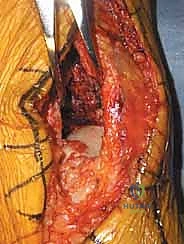

الإدارة المرحلية (Staged Management): سر النجاح وتجنب الكوارث

أكبر خطأ يمكن أن يرتكبه جراح العظام في كسور البيلون عالية الطاقة هو إجراء الجراحة النهائية (ORIF) في يوم الإصابة. الجلد المتورم والأنسجة المتهتكة لا تتحمل الشقوق الجراحية، ومحاولة إغلاق الجلد فوق الشرائح المعدنية ستؤدي حتماً إلى تمزق الجرح، انكشاف العظم، وعدوى عميقة قد تنتهي ببتر القدم.

لتجنب ذلك، يتبع الأستاذ الدكتور محمد هطيف بروتوكولاً صارماً يُعرف بـ الإدارة المرحلية:

المرحلة الأولى: التثبيت الخارجي المؤقت (Spanning External Fixator)

تتم هذه المرحلة كإجراء طارئ في يوم الإصابة أو اليوم التالي.

* يتم تركيب إطار معدني خارجي (المثبت الخارجي). يتم إدخال دبابيس معدنية في عظم الظنبوب السليم (تحت الركبة)، ودبابيس أخرى في عظام القدم (عظم العقب أو مشط القدم).

* يتم سحب القدم (Traction) لاستعادة طول الساق المفقود وإبعاد العظام المفتتة عن بعضها (مبدأ Ligamentotaxis).

* الهدف: تثبيت العظام، تخفيف الألم، والأهم: السماح للأنسجة الرخوة بالتعافي، وزوال التورم، وشفاء فقاعات الكسر.

المرحلة الثانية: التخطيط الجراحي الدقيق (Pre-operative Planning)

قبل دخول غرفة العمليات لإجراء الجراحة النهائية، يقوم الدكتور هطيف برسم خطة تفصيلية. يتم استخدام الأشعة المقطعية لتحديد أماكن الشقوق. القاعدة الذهبية هي: يجب أن يكون هناك مسافة لا تقل عن 7 سنتيمترات بين أي شقين جراحيين (مثلاً شق للشظية وشق للظنبوب) لضمان عدم انقطاع التروية الدموية عن الجلد بينهما (Skin Bridge).

الخطوات الجراحية التفصيلية: إبداع التثبيت الداخلي المفتوح (ORIF)